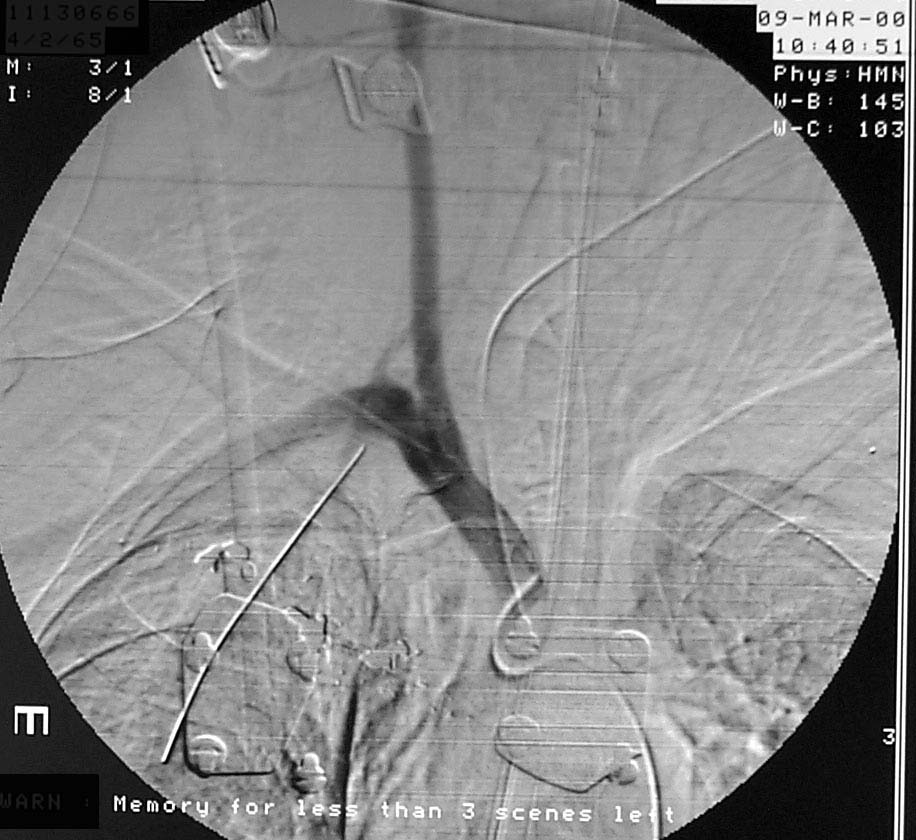

Enclosed are three figures--the CXR of a male with a left to right transmediastinal GSW of upper chest--no hard signs of vascular injury except for about 1000 cc blood out of left chest tube which eventually stopped without surgery. Next is angio #1 showing intimal defect in innominate artery right at the takeoff of the Rt subclavian and carotids. F/U angio one week later--no surgery--documents complete resolution of the intimal injury. There were no symptoms, including the blood from the left chest, attributable to this injury, thus fulfilling the criteria for observation.

Angio (1 week)